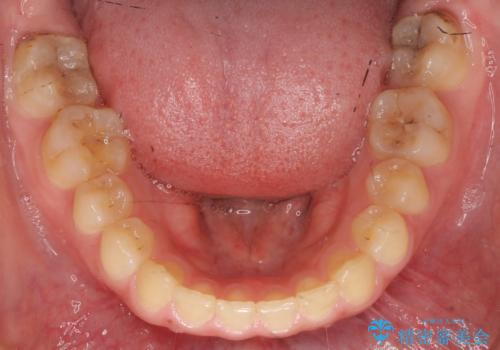

前歯のがたつき 過蓋咬合

- 20代女性

今回は上の前歯が内側に傾いている症状があり(Angle Ⅱ級2類)、その修正に時間がかかっています。

一見同じような歯並びに見えても、前歯の角度や、奥歯の上下の噛み合わせによって難易度には差があります。